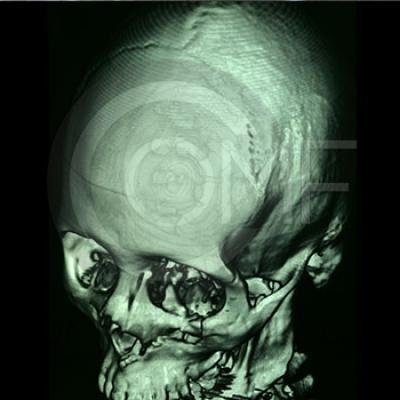

Fractura de Malar